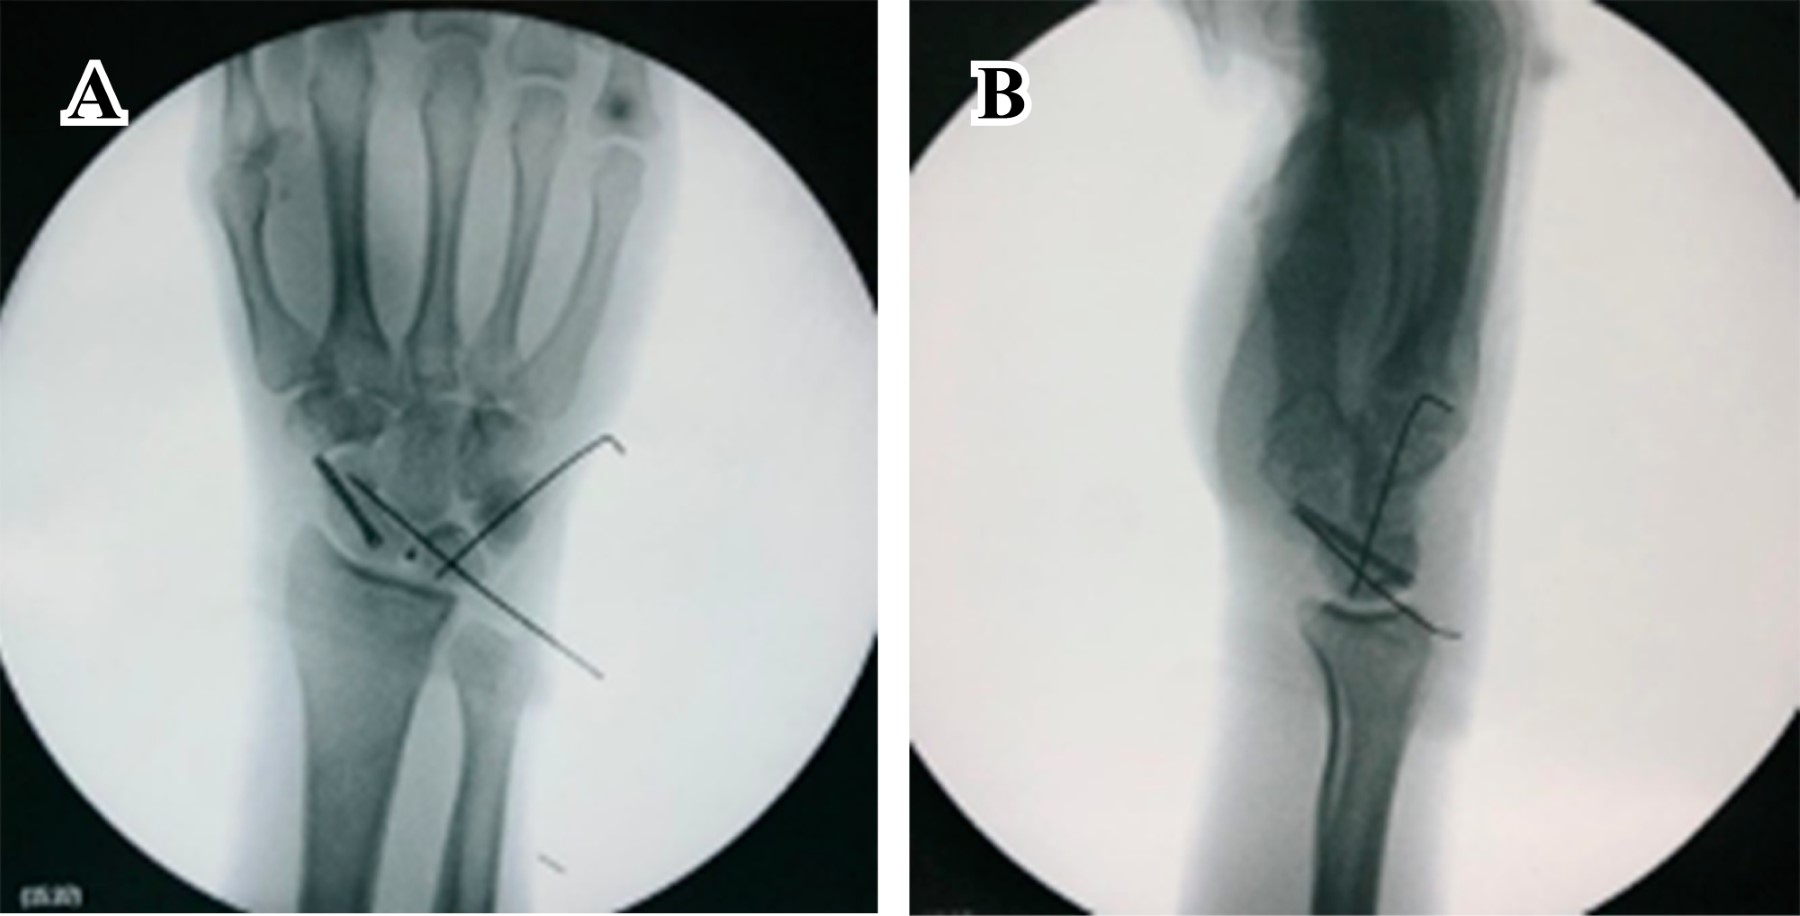

Masculino de 23 años de edad, sano, quien sufre caída del propio plano de sustentación contundiendo mano derecha con mecanismo de hiperflexión. Inicia con dolor, limitación funcional y edema importante en muñeca, motivo por el cual acude al servicio de urgencias. A la exploración física, llama la atención edema y deformidad en dorso de muñeca derecha con limitación funcional a expensas del dolor, sin alteraciones neurovasculares distales. Se realizan radiografías en proyecciones anteroposterior y oblicua de mano (Figura 1); se observa incongruencia entre líneas carpales con sospecha de fractura de escafoides. Se realiza tomografía computarizada (Figura 2), con la cual se completa diagnóstico de fractura luxación transescafo-perilunar.

Figura 2